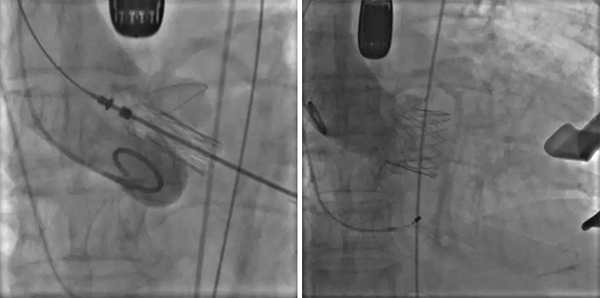

4月28日上午,手术在我院介入中心开始实施。邹承伟教授挂帅,心脏大血管外科王正军主任医师及张骞主治医师上台,心内科田洪波副主任医师经患者右侧颈内静脉置入心内膜起搏电极备用并负责起搏器的调试;麻醉科王萍、王旭副主任医师负责麻醉与监护;超声科郭文彬主任全程食道超声监测;介入中心李敏护士长带领导管室的护士们;焦琦琦等手术室的护理人员全方位密切配合;在郭应强教授的亲自指导下,整个手术过程衔接紧密,操作流畅,1小时左右即告完成,主要步骤仅用时20余分钟,术中基本无出血。食道超声检查显示瓣膜位置及功能良好,无瓣周漏及反流,冠状动脉显影良好,心电监护示心电图与术前比无变化,血压脉压差恢复到正常范围。